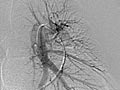

La angiografía pulmonar es una radiografía que utiliza un tinte especial y una cámara (fluoroscopia) para tomar imágenes del flujo sanguíneo en los vasos sanguíneos de los pulmones.

La angiografía pulmonar se usa para evaluar las arterias que van a los pulmones (arterias pulmonares) y los vasos sanguíneos en los pulmones. También puede detectar el estrechamiento o la obstrucción de un vaso sanguíneo que reduce o detiene el flujo de sangre.

La angiografía pulmonar es una radiografía que utiliza un tinte especial y una cámara (fluoroscopia) para tomar imágenes del flujo sanguíneo en los vasos sanguíneos de los pulmones. Es posible que su médico le comunique algunos resultados inmediatamente después de la prueba. Por lo general, los resultados completos están listos el mismo día.

El material de contraste fluye en forma pareja a través de los vasos sanguíneos.

No se observa estrechamiento, obstrucción, abultamiento ni otro problema en los vasos sanguíneos. Las presiones arteriales pulmonares son normales.